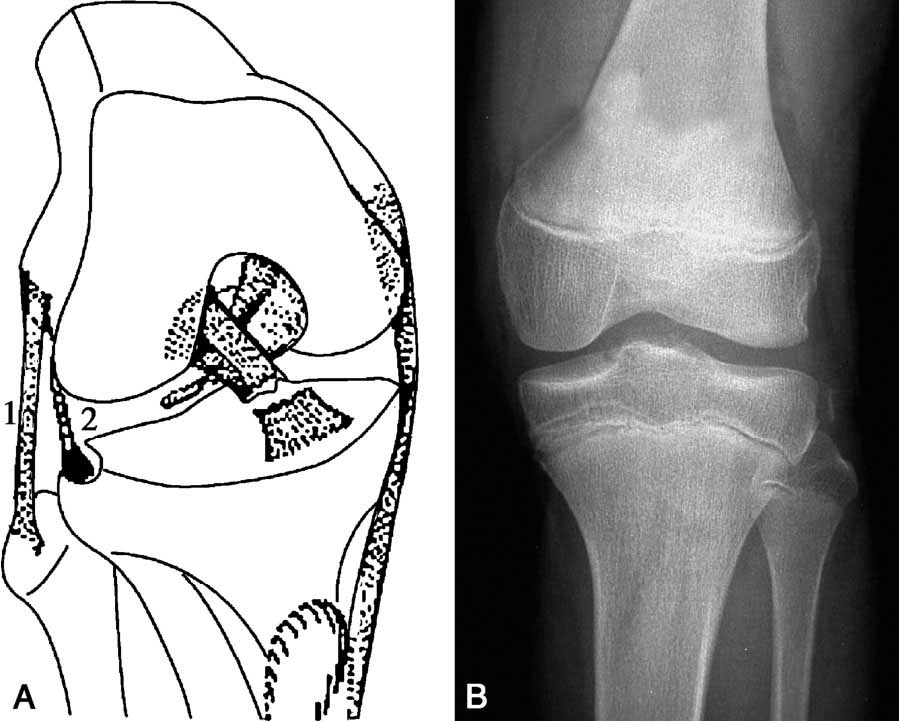

Segond骨折

A.1.腓侧副韧带;2.外侧关节囊韧带撕脱骨折。B.X线片

在此还需注意一特殊意义的骨折:Segond骨折,是指胫骨平台外侧的撕脱骨折,也称外侧关节囊征,经常出现在新鲜的膝关节损伤中(图12-5-7A)。撕脱的骨片是与外侧关节囊的中央部分或外侧半月板胫骨韧带相连,骨片的形状多为椭圆形,X线表现骨片距关节水平平均为4mm。Segond骨折是一个重要的放射学征象,它出现时几乎都伴随着前十字韧带的损伤。文献报道,Segond骨折合并前交叉韧带损伤的发生率为75%~100%。北京积水潭医院回顾了2000—2005年间510例前交叉韧带损伤的病例,Segond骨折发生率为7.6%,Segond骨折合并前交叉韧带损伤的发生率为95.1%。